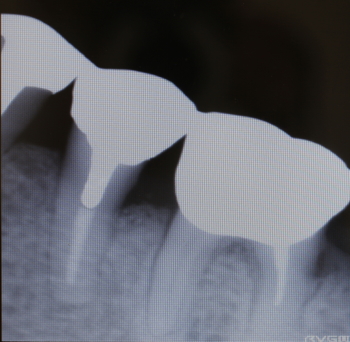

35番遠心より排膿

同部のX-ray

骨補填剤充填後のX-ray

2016年07月21日撮影

術後約3.5カ月後

予後良好